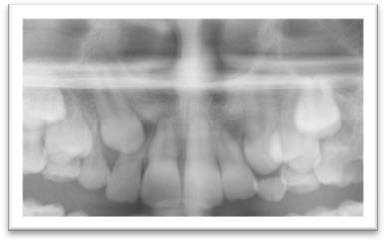

Canine(s) incluse(s) avec risque de résorption de l'incisive latérale